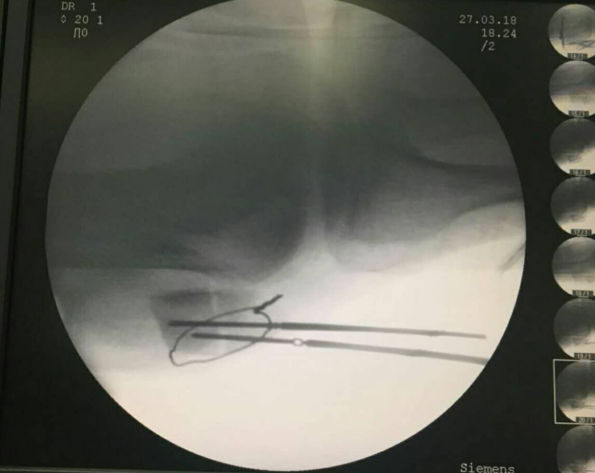

先扪及髌骨上下极及断端,用电钻于髌骨上极打一骨洞

利用腰穿针带过钢丝

再用利用腰穿针引导钢丝

收紧钢丝打结使其骨折端复位,透视发现复位欠佳

继续收紧钢丝,骨折复位,剪断钢丝

将钢丝埋于深处

由下方两钢丝口打入两髌骨